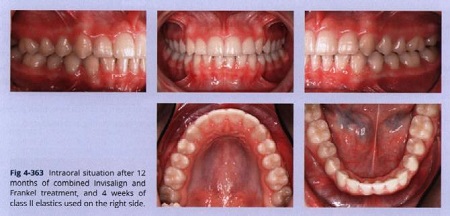

Hình 4-363 chỉ ra tình trạng sau 12 tháng khi kết hợp máng chỉnh nha trong suốt và điều trị Frankel với 4 tuần đeo chun loại II ở bên phải. Một duy trì mặt lưỡi được dính ở cung hàm dưới từ răng 33 đến 43 và bệnh nhân đeo cung hàm trên với khay trong suốt cuối trong 3 giờ vào ban ngày và đeo Frankel vào buổi tổi để duy trì trong 4 tháng.

Sau giai đoạn này, việc duy trì được thực hiện với duy trì mặt lưỡi ở cung hàm dưới và khay trong suốt được tháo lắp ở cung hàm trên vào buổi tối.